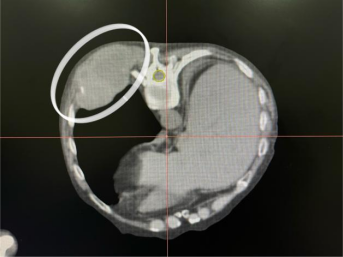

患者肿瘤体积较大,周围血管丰富,且进针最大深度达到了皮下10cm。在麻醉手术中心王莉副主任医师的协助下,杨金平副主任借助定位CT引导,成功将插植针顺利插入肿瘤部位 。

杨金平副主任勾画肿瘤靶区,有效保护周围重要危及器官的同时,给予肿瘤治疗足够的放射处方剂量;物理师徐杨根据剂量要求,按照插植放疗计划,进行插植治疗, 所有流程都在计划当中有序进行。